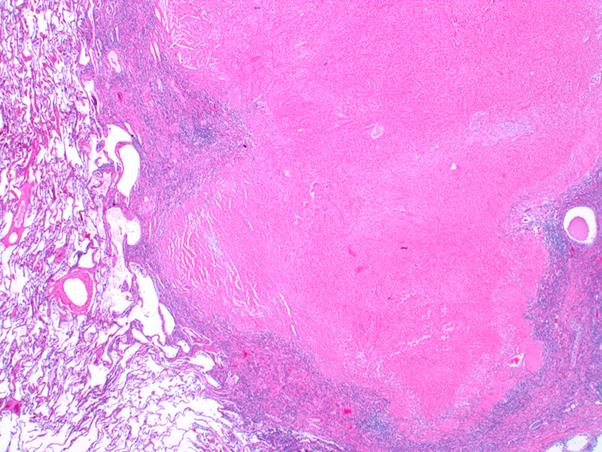

Complete pathologic response of metastatic cutaneous squamous cell carcinoma and allograft rejection after treatment with combination immune checkpoint blockade.

JAAD Case Rep. 2017 Sep 8;3(5):412-415. doi: 10.1016/j.jdcr.2017.06.005. eCollection 2017 Sep.

DOI:10.1016/j.jdcr.2017.06.005

PMID:28932782

原文链接:https://pmc.ncbi.nlm.nih.gov/articles/PMC5594230/